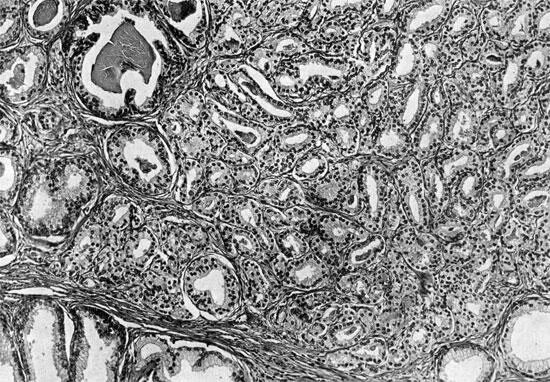

Высокодифференцированная аденокарцинома кишки